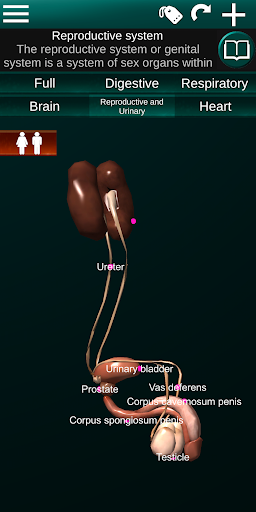

* Reproductive system, which includes the male and female reproductive organs.

* Compare male and female organs.